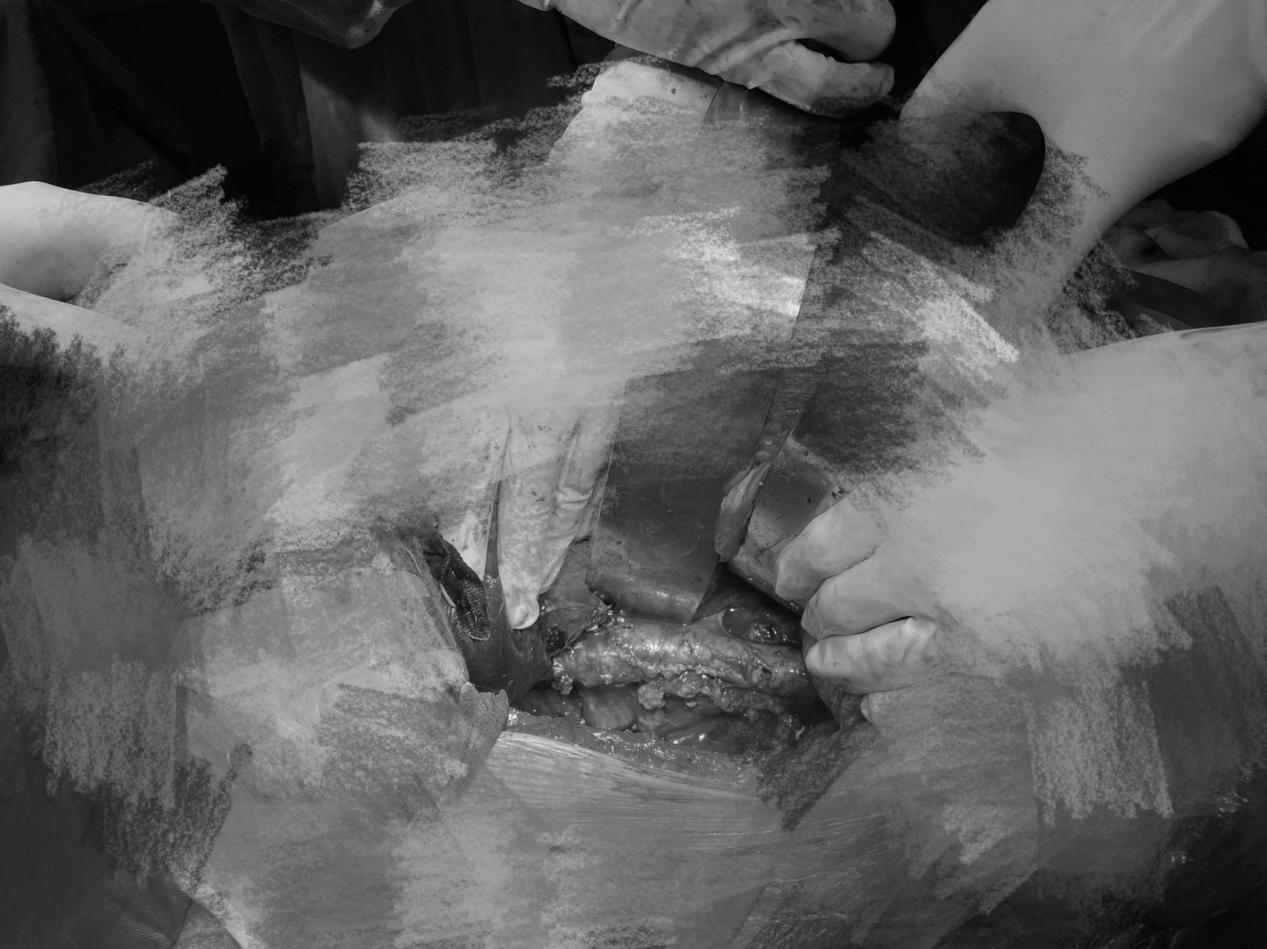

面对挑战,刘飞教授带领团队迎难而上,术前做好科室讨论,同时组织血管外科、肝胆外科、麻醉与围术期医学科和医学影像中心等兄弟科室进行多学科 MDT 讨论,研究手术方案和细节,充分完善各种应急预案,为患者制定周密细致的手术计划。考虑患者既往胆道开放手术史,刘飞教授带领团队于 2021 年 11 月 12 日在全麻下,联合肝胆外科和血管外科,成功实施右肾癌根治术+下腔静脉癌栓取出术。

患者术后恢复良好,术后第二天即肛门排气,住院期间未出现任何并发症,现已康复出院。